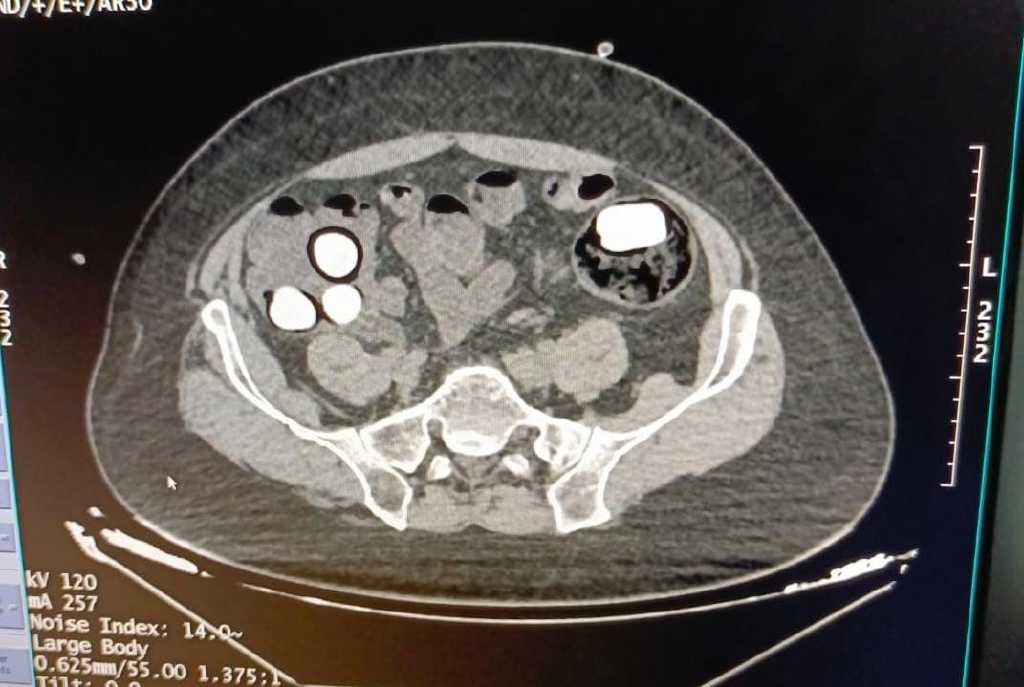

Gözaltına alınan yabancı uyruklu 2 kişiye, hastanede yapılan incelemeler sonucunda midelerinde 126 kapsül halinde 1 kilo 300 gram eroin ve 44 kapsül halinde 550 gram afyon sakızı olduğu görüldü.

Uyuşturucular, hastanedeki müdahalenin ardından şüphelilerin midesinden çıkarıldı. Y.S. ve H.S., emniyetteki işlemlerinin ardından çıkarıldıkları mahkemece tutuklanarak cezaevine gönderildi.